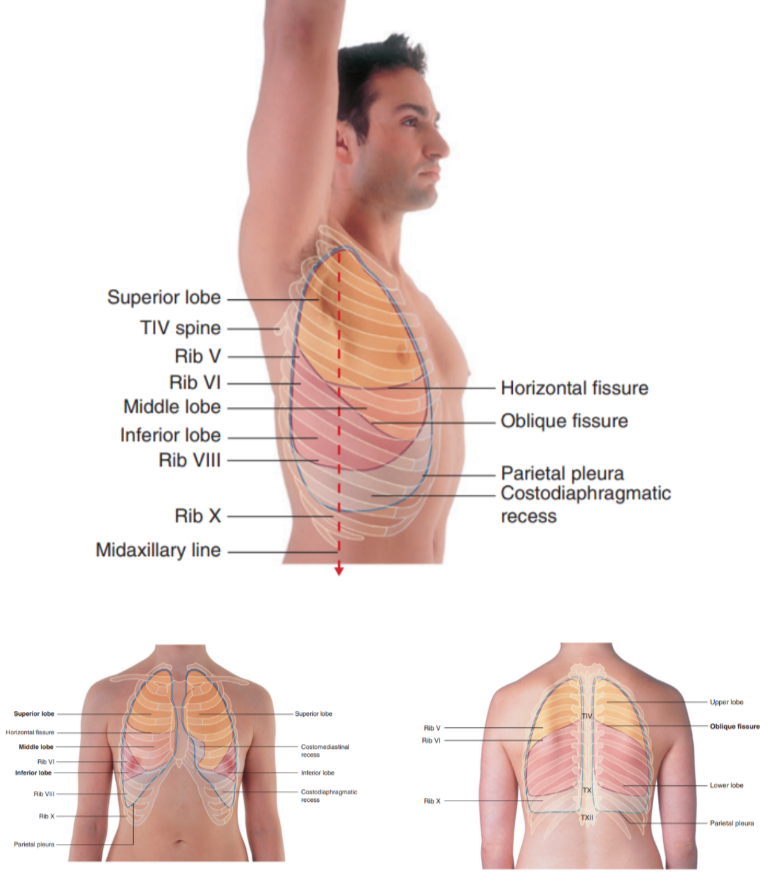

Surface anatomy relating to the fissures and lobes

Palpable surface landmarks —

Can be used to visualize the normal outlines of the pleural cavities & lungs & to determine the positions of the pulmonary lobes & fissures —ex.

Superiorly, we can see the parietal pleura projects above the first costal cartilage & anteriorly approaches the midline posterior to the sternum (uppermost section). Left parietal pleura doesn’t come close to the midline as much as the right lobe due to the heart bulging on the left side

Inferiorly, the pleura reflects on the diaphragm, above the costal margin & courses around the thoracic wall following an VIII, X, XII contour

(Ie. rib VIII in the midclavicular line, rib X in the midaxillary line, and vertebra TXII posteriorly)

Lungs don’t completely fill areas surrounded by pleural cavities — particularly anteriorly & inferiorly —

Costomediastinal recesses —

Occur anteriorly, particularly on the left side in relationship to the heart bulge

Costodiaphragmatic recesses —

Occur inferiorly between the lower lung margin & the lower margin of the pleural cavity

Margins of lungs related to ribs

Inferior lung margin —

Found at bottom of the thoracic wall, following a VI, VIII, X contour (ie. rib VI in the midclavicular line, rib VIII in the midaxillary line, and vertebra TX posteriorly)

Oblique fissure position —

Located in the midline, near the spine of vertebrae TIV, moves laterally downwards crossing fourth and fifth intercotal spaces and reaches VI laterally

Horizontal fissure(right side) —

Follows the contour of rib IV and its costal cartilage

Oblique fissures on both sides follow the contour of rib VI and its costal cartilage